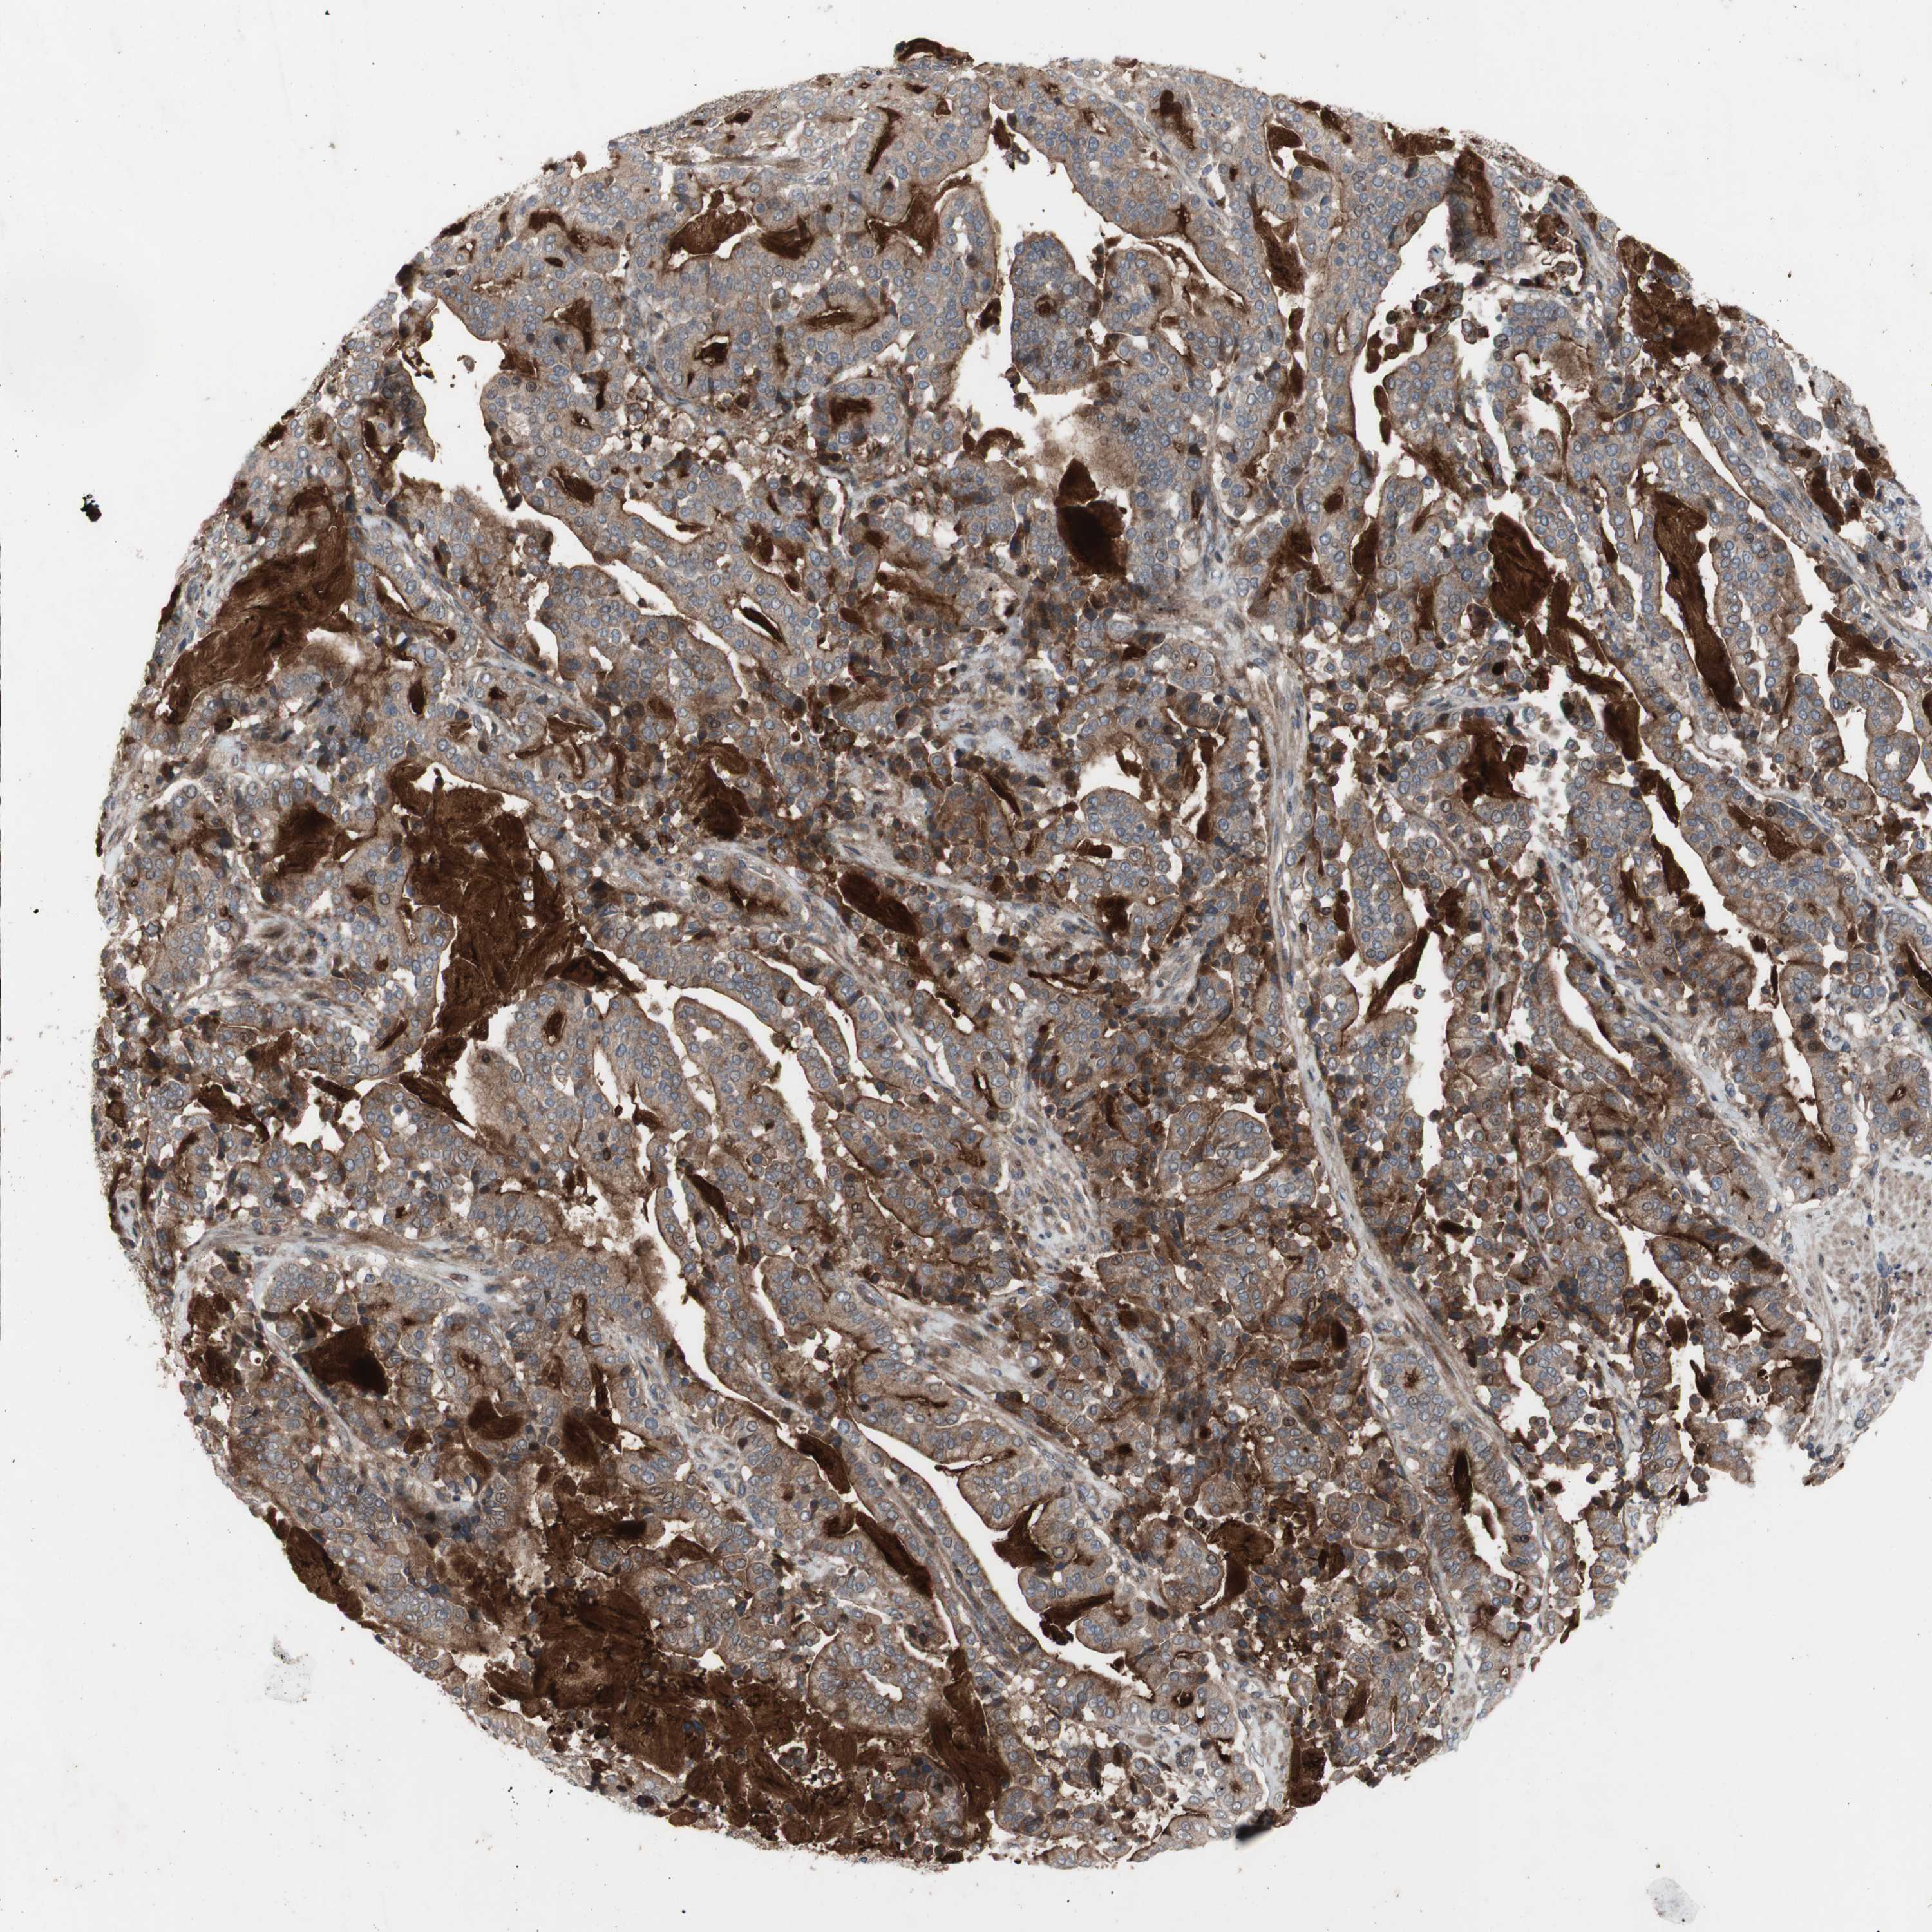

PANCREATIC CANCER - Protein expressioni

A mouse-over function shows sample information and annotation data. Click on an image to view it in a full screen mode. Samples can be filtered based on level of antibody staining by selecting one or several of the following categories: high, medium, low and not detected. The assay and annotation is described here.

Note that samples used for immunohistochemistry by the Human Protein Atlas do not correspond to samples in the TCGA dataset.

Antibody stainingi

Antibody staining in the annotated cell types in the current human tissue is reported as not detected, low, medium, or high, based on conventional immunohistochemistry profiling in selected tissues. This score is based on the combination of the staining intensity and fraction of stained cells.

Each image is clickable and will lead to virtual microscopy that enables deeper exploration of all samples and also displays staining intensity scores, fraction scores and subcellular localization as well as patient and tissue information for each sample.

Antibody HPA009291

Staining

High

Medium

Low

Not detected

Intensity

Strong

Moderate

Weak

Negative

Quantity

>75%

75%-25%

<25%

None

Location

Nuclear

Cytoplasmic/membranous

Cytoplasmic/membranous,nuclear

Adenocarcinoma, NOS